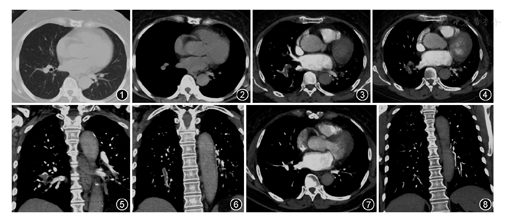

入院体检:脉搏78次/min,呼吸19次/min,血压107/70 mmHg(1 mmHg=0.133 kPa),血氧饱和度(自然状态)97%。双肺呼吸音清,未闻及干湿性啰音。心腹及神经系统阴性。双下肢无水肿。实验室检查:血常规示白细胞为9.9×109/L,中性粒细胞为0.62,血红蛋白为132 g/L,血小板为332×109/L。C反应蛋白为14.0 mg/L。凝血功能示凝血酶原时间(PT)10 s,活化部分凝血活酶时间(APTT)32.6 s,D-二聚体为463 μg/L。血气分析示pH值为7.44,PaO2为80 mmHg,PaCO2为37 mmHg。B型钠尿肽(BNP)6.1 ng/L。诱导痰嗜酸粒细胞<2.5%,支气管激发及舒张试验均阴性。心电图未见异常。患者慢性咳嗽2年,多次胸部CT均未报异常,仔细观察胸部CT发现右肺下叶肺动脉似有增宽,结合患者活动后胸闷气促及髋关节置换手术史,于2016年2月29日行CT肺动脉造影(CT pulmonary angiography,CTPA)示主肺动脉、左右肺动脉干及各大血管大小形态如常,血管走形自然、管腔显影良好,两侧段及亚段肺动脉分支见多发低密度充盈缺损影(图3, 图4, 图5, 图6),考虑肺栓塞。同时完善双下肢深静脉B超示双下肢深静脉通畅。超声心动图示右心房室不大,肺动脉不增宽,连续多普勒根据轻微三尖瓣反流估测肺动脉收缩压约20 mmHg。多次复查D-二聚体均<500 μg/L。

患者无休克或持续性低血压,无右心功能不全,按简化版肺栓塞严重指数(sPESI)临床预后风险评分为0分,属于低危组,根据我国最新急性肺栓塞诊断与治疗中国专家共识[3]按体重给予低分子肝素钙(0.6 ml,1次/12 h)皮下注射联合华法林钠(2.5 mg,1次/d)口服抗凝治疗,多次复查凝血功能至INR达2~3之间停用低分子肝素钙,出院后继续口服华法林钠(2.5 mg,1次/d)治疗,叮嘱患者定期复查凝血功能,动态监测INR使其控制在2~3之间,经抗凝治疗2个月后复查CTPA显示段及亚段肺动脉分支通畅,未见血栓形成(图7,图8),且患者自诉咳嗽症状较前明显改善,继续使用4个月后停用华法林钠。